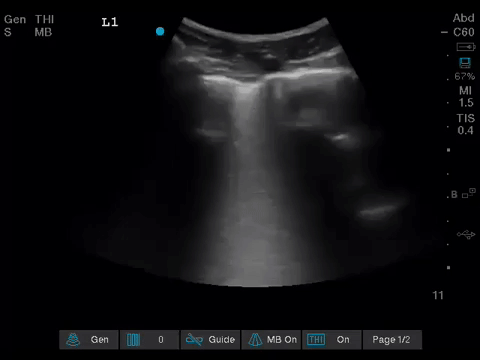

The POCUS team was asked to specifically to assess her lungs to help determine the cause of her dramatically increased oxygen requirements.

Before giving their clinical interpretation of the LUS findings, the POCUS team also scanned the heart and vasculature to obtain a more complete picture.

1. When scanning the lungs, a comprehensive, bilateral lung scan is far superior to a single clip; as this will offer more information and permit an interpretation based on the overall pattern of findings. Had this patient only had the R1 area scanned, for example, we may have reached the erroneous conclusion that her hypoxemia was likely due to pulmonary edema.